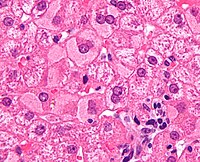

Imaging tests such as transient elastography, ultrasound and magnetic resonance imaging can be used to show the liver tissue and the bile ducts. Liver biopsy can be performed to examine liver tissue to distinguish between various conditions; tests such as elastography may reduce the need for biopsy in some situations.[47]

A previously undiagnosed liver disease may become evident first after autopsy.[citation needed] Following are gross pathology images: